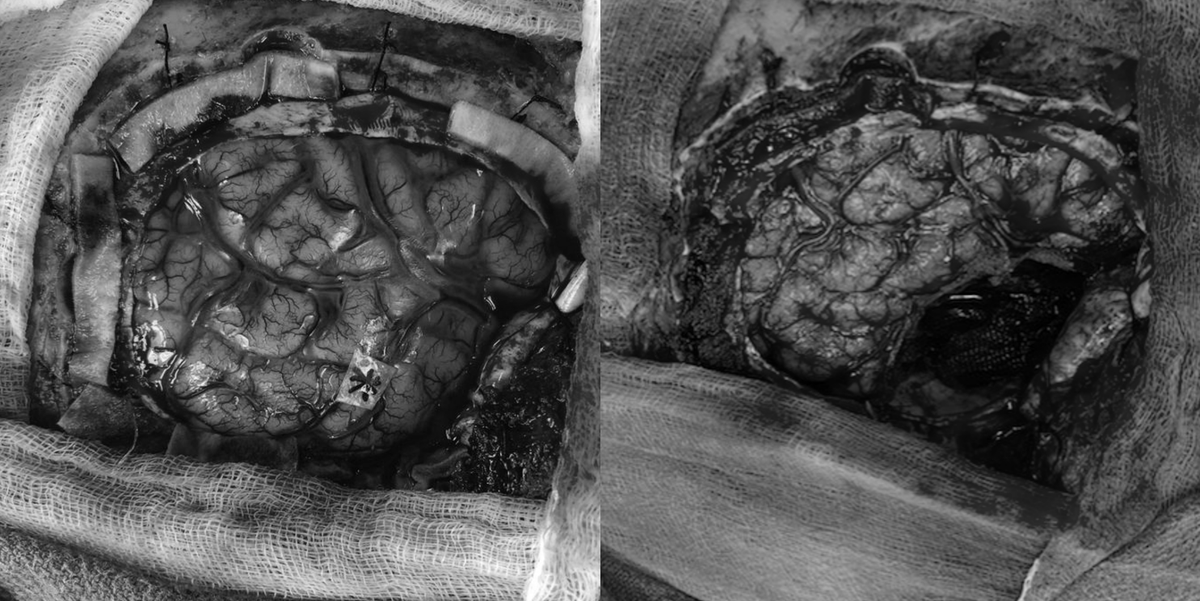

Beautiful depiction of electrical activity in the brain merging MRI and EEG data, designed in 2016 by @neuroscapeucsf @UCSF

MD, MSc, FRCSC| Functional and Epilepsy Neurosurgeon @UOttawa| @Emoryneurosurg & @westernu_nsx Alumnus| M.D. @uoftmedicine | MSc @uwaterloo. #medtwitter